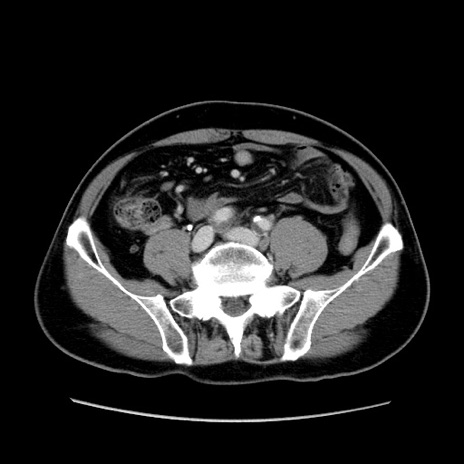

症例34(横断像)

【症例】60歳代 男性

【主訴】右鼠径部膨隆

【現病歴】1年程前より右鼠径部膨隆あり。自己にて還納可能だったため放置していた。3時間前より右鼠径部の脱出を認め、還納困難となり受診。

【身体所見】右鼠径部に小児頭大の膨隆あり。弾性硬であり、用手還納は困難。左鼠径部にも膨隆を認める。脱出はなし。